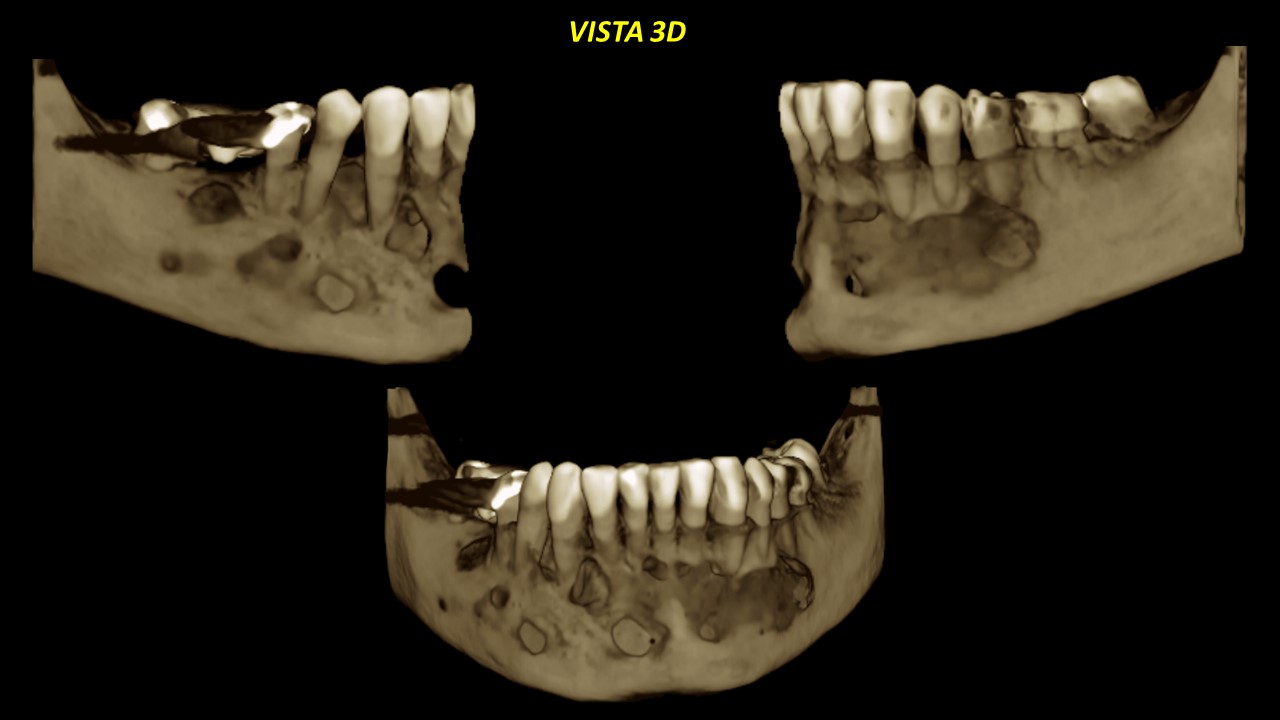

Figura 8

Figura 9

Signos tomográficos a descartar probable recurrencia de lesión quística (Queratoquiste Odontogènico). Esta entidad también puede ser observada de manera clara en las diferentes reconstrucciones tridimensionales resaltando sus características. (Figuras 8 y 9).